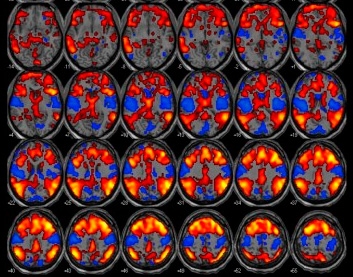

Imagem: Agência Fapesp / Instituto Brainn. Ressonância magnética funcional mostrando a ativação de neurônios de uma pessoa durante o sono nas áreas vermelhas e azuis.